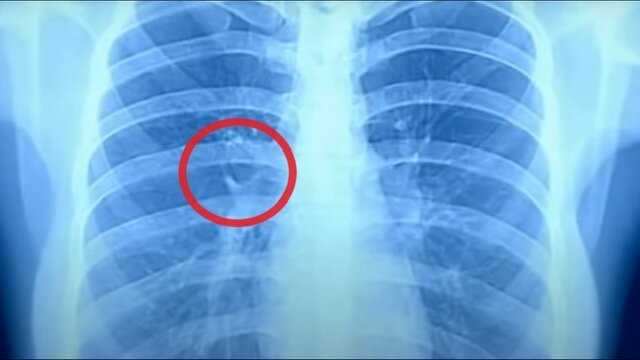

При коронавирусной инфекции у многих начинается ковидная пневмония. В результате из-за воспаления ткани в легких могут рубцеваться, то есть на них образуются шрамы.

Эти участки становятся жесткими и не могут насыщать кровь кислородом. Площадь легких уменьшается. Врачи называют это состояние пневмофиброзом.

Пострадавшего мучает сухой кашель и отдышка, становится тяжело дышать, особенно при ходьбе и физической нагрузке.